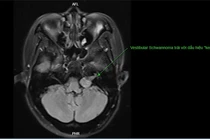

Bệnh nhân có tiền sử chấn thương vùng đầu – mặt, kèm các biểu hiện bất thường như đỏ mắt, lồi mắt, ù tai cần được khám chuyên khoa ngay. Dò động mạch cảnh xoang hang nếu không điều trị sớm có thể dẫn đến các biến chứng nghiêm trọng.